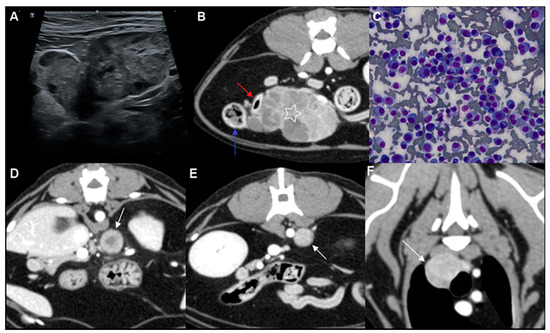

Multicentric Round Cell Neoplasia with Plasmacytic Differentiation in a Cat with Systemic Progression: Multimodal Imaging and Treatment Response

Plasma cell neoplasia is uncommon in cats, and multicentric nodal-predominant involvement has not been well characterized. This report describes a multicentric round cell neoplasia with plasmacytic differentiation in a 14-year-old Domestic Shorthair cat, emphasizing multimodal imaging features and treatment response. Contrast-enhanced computed tomography [...] Read more.

Plasma cell neoplasia is uncommon in cats, and multicentric nodal-predominant involvement has not been well characterized. This report describes a multicentric round cell neoplasia with plasmacytic differentiation in a 14-year-old Domestic Shorthair cat, emphasizing multimodal imaging features and treatment response. Contrast-enhanced computed tomography and magnetic resonance imaging were performed for staging and longitudinal assessment. Cytomorphology supported plasmacytic differentiation, and flow cytometry did not demonstrate an immunophenotype consistent with conventional B- or T-cell lymphoma. Because histopathology, immunohistochemistry, bone marrow evaluation, and assessment for monoclonal gammopathy were not performed, definitive classification was not possible; however, cytomorphology supported plasmacytic differentiation, with plasma cell neoplasia remaining an important diagnostic consideration. A hypofractionated radiotherapy protocol (36 Gy in six fractions) combined with systemic chemotherapy was administered. Serial imaging demonstrated complete radiologic resolution of the irradiated mass, whereas non-irradiated presumed nodal lesions progressed and an extradural spinal lesion subsequently developed. These findings highlight the capacity of round cell neoplasia with plasmacytic differentiation to mimic lymphoma on imaging and illustrate the dissociation between effective local control and ongoing systemic progression. Full article

(This article belongs to the Special Issue Abdominal Imaging in Small Animals: New Insights)

Show Figures

Figure 1